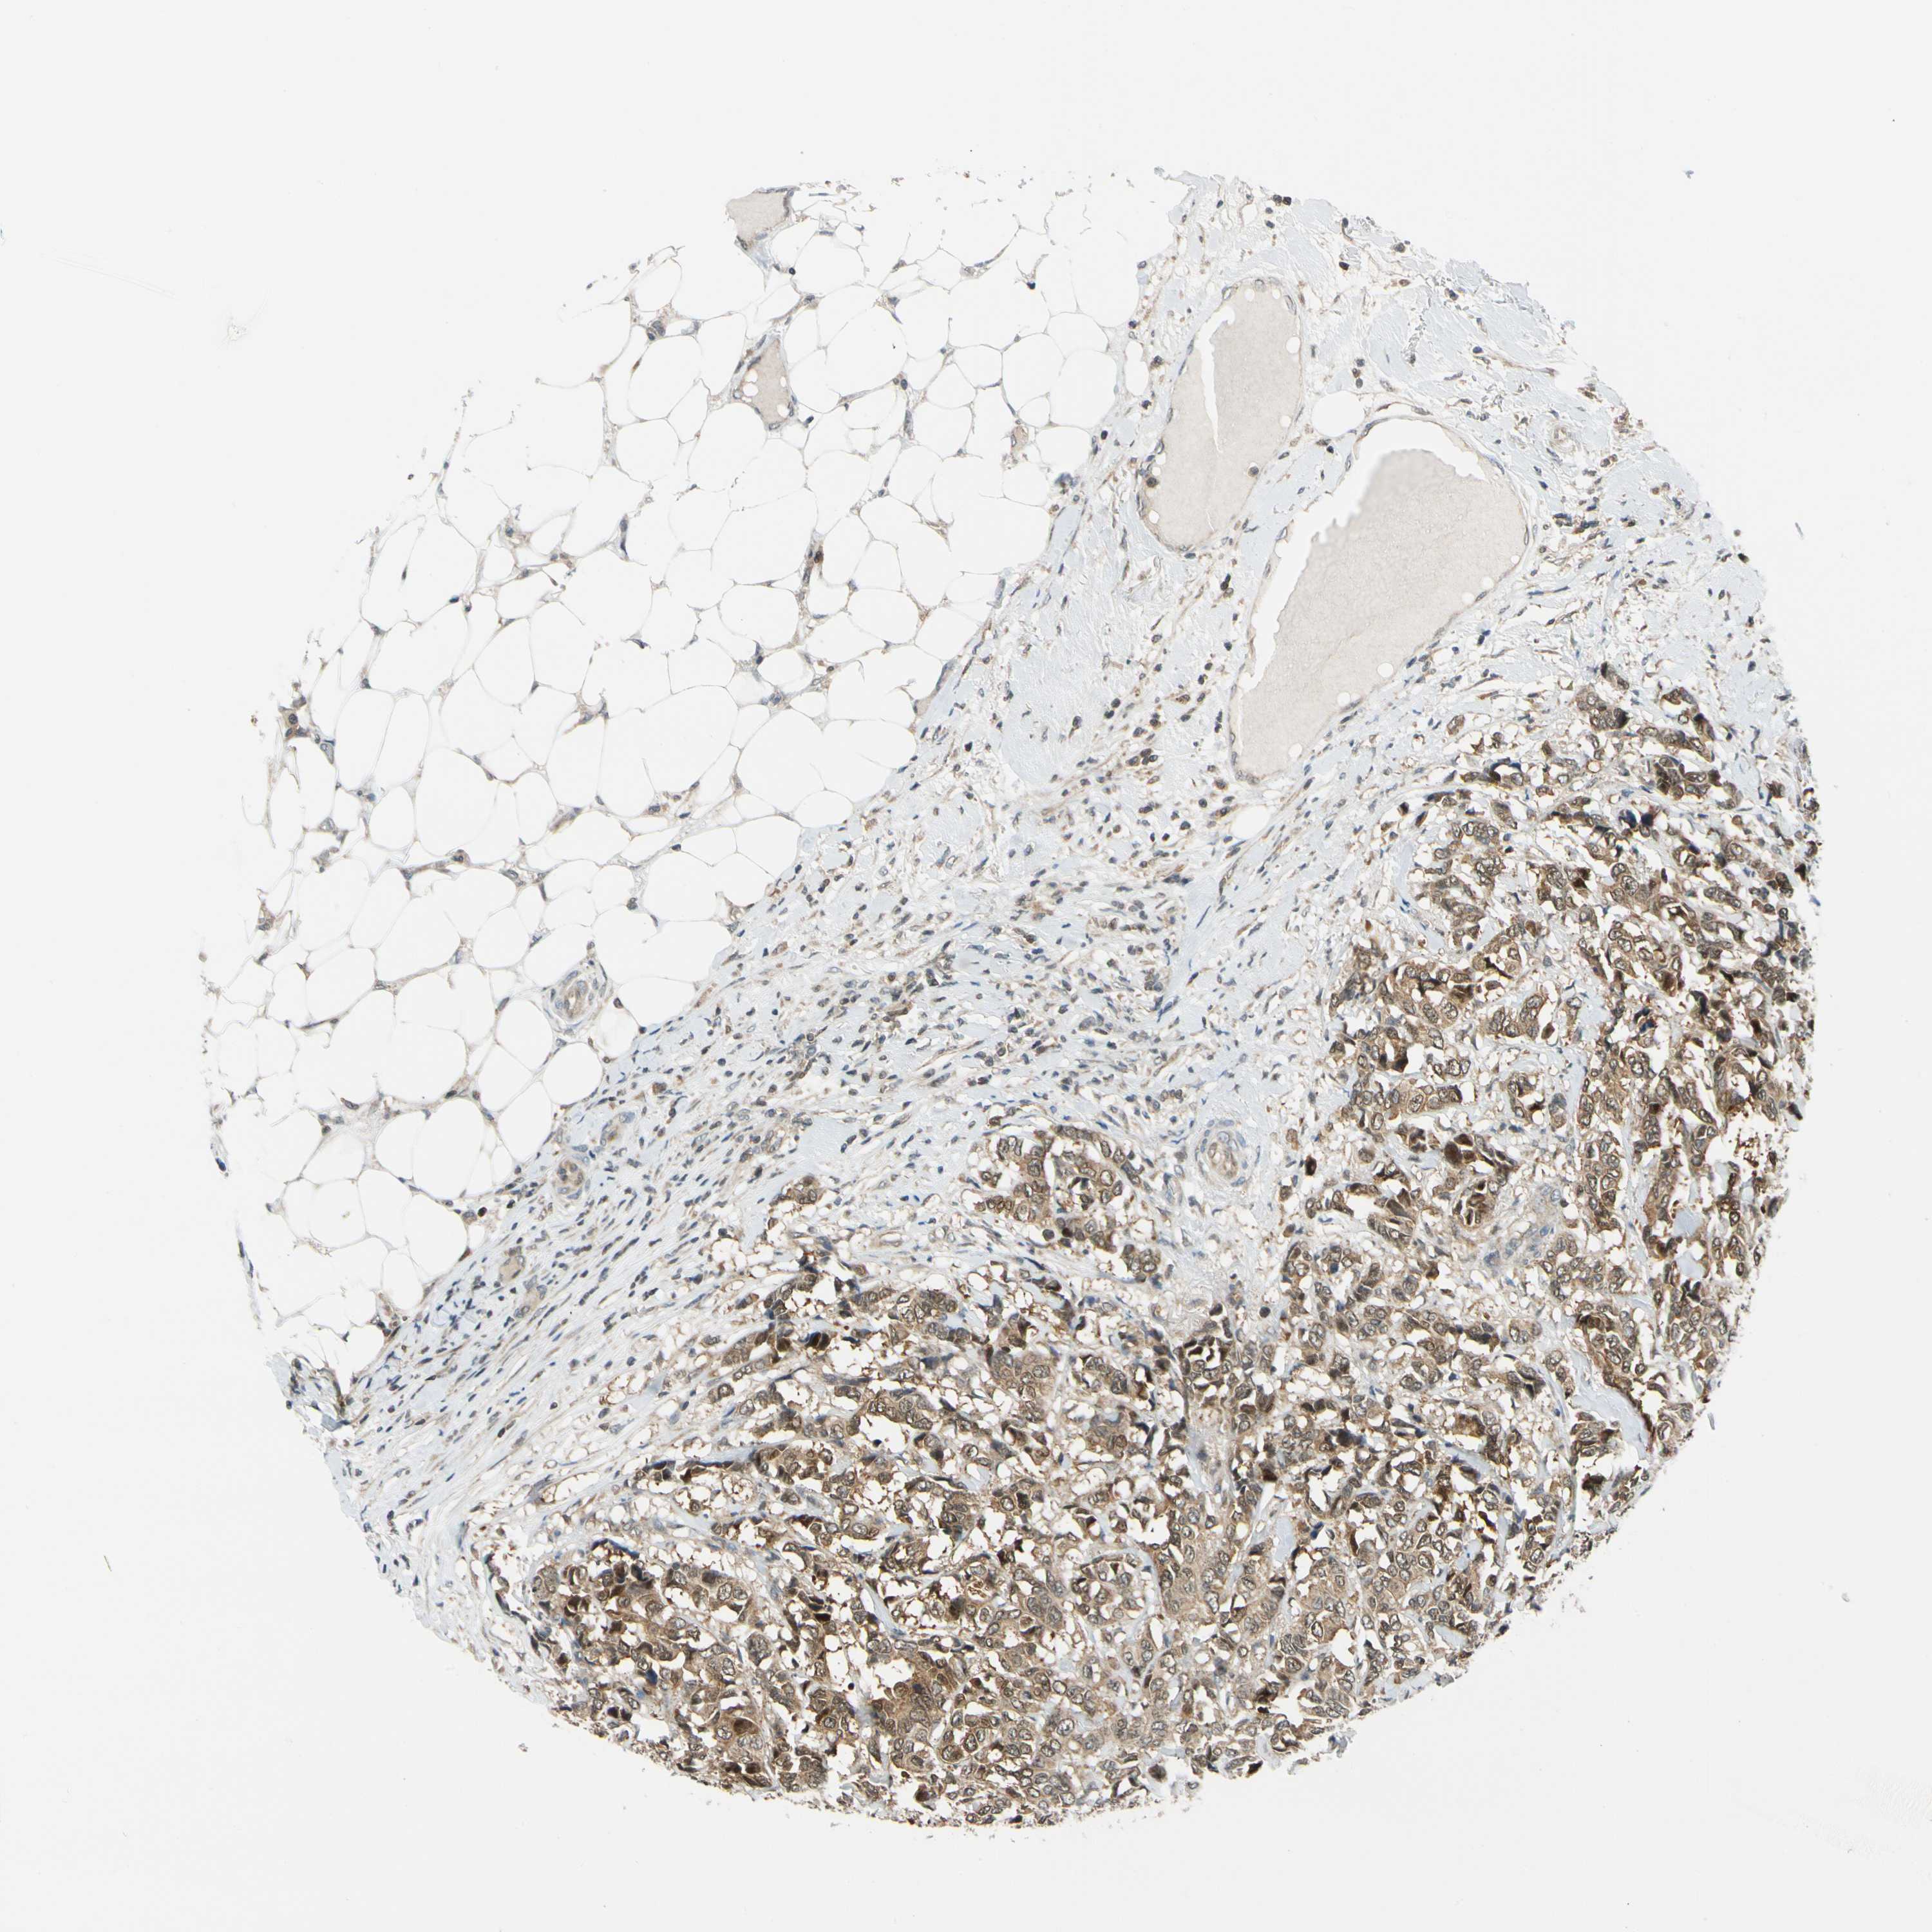

BRCA TCGA BRCA VALIDATION PROTEIN EXPRESSION